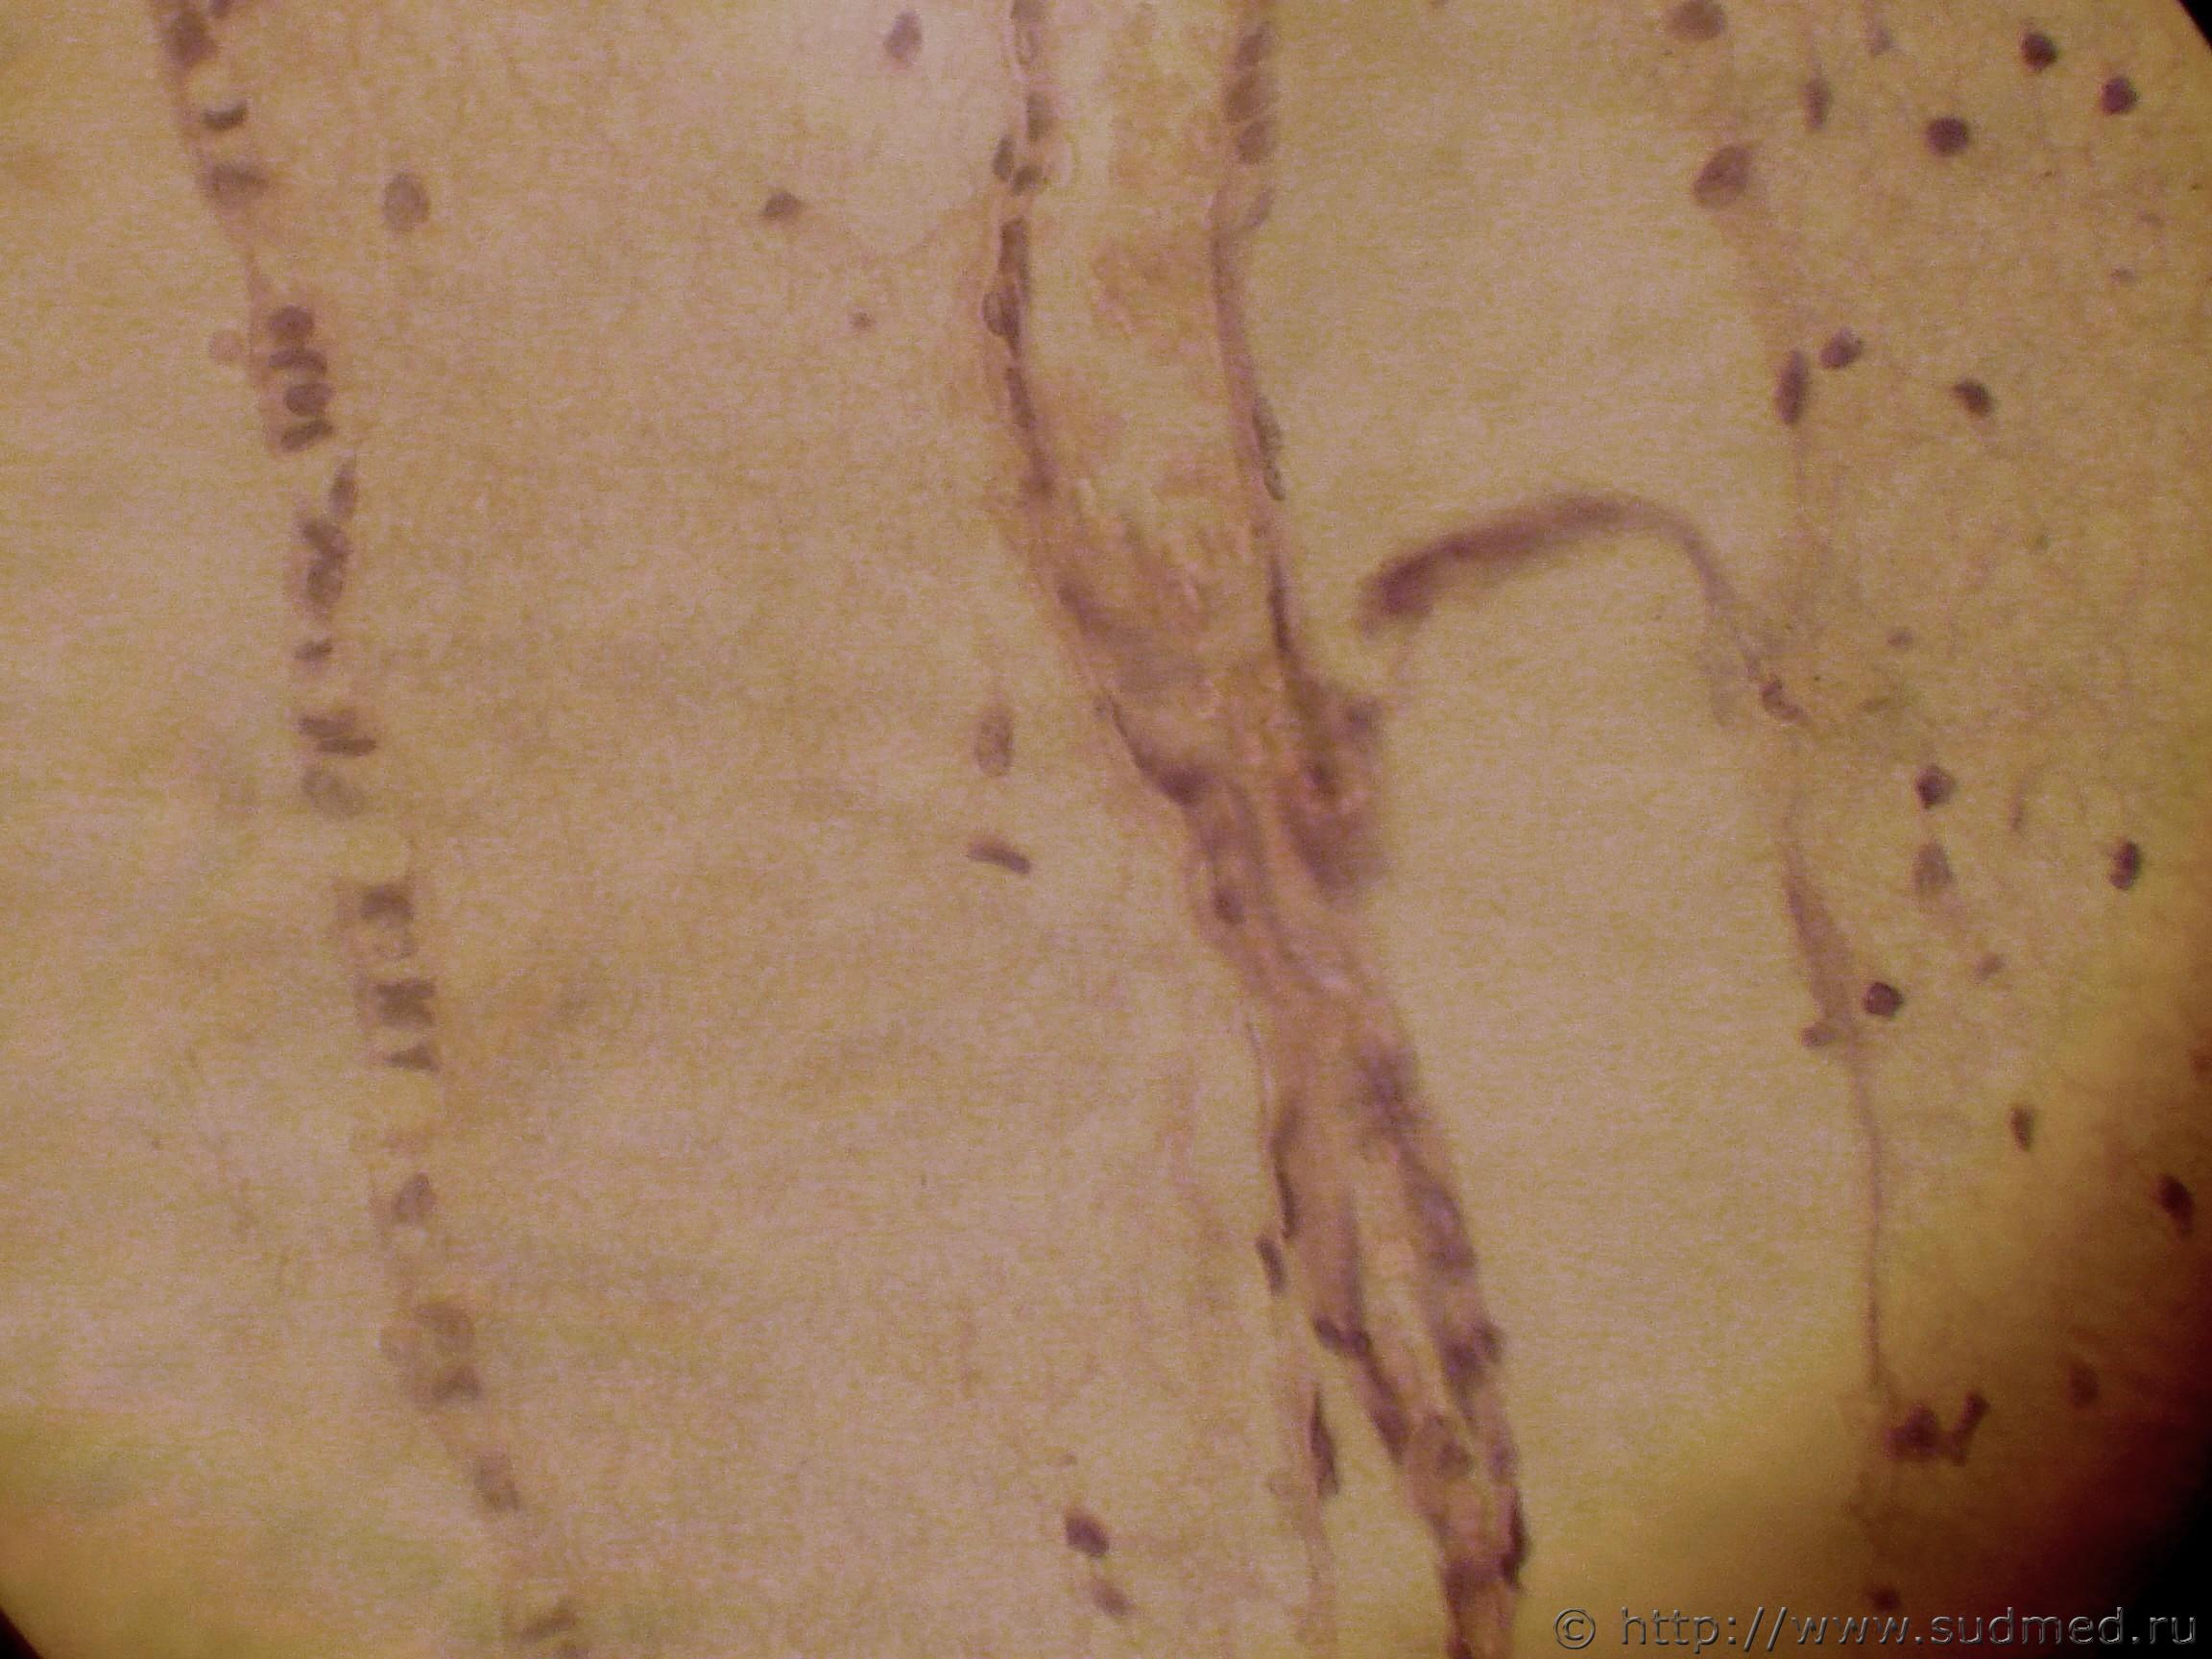

болезнь Крейтцфельдта-Якоба (Во Франции встречается спорадически, вскрытие проводится как при особо опасных инфекциях, весь используемый материал подлежит специальному инструктажу по уничтожению)

Гистологически отмечается спонгиозность ткани головного мозга

срез 3